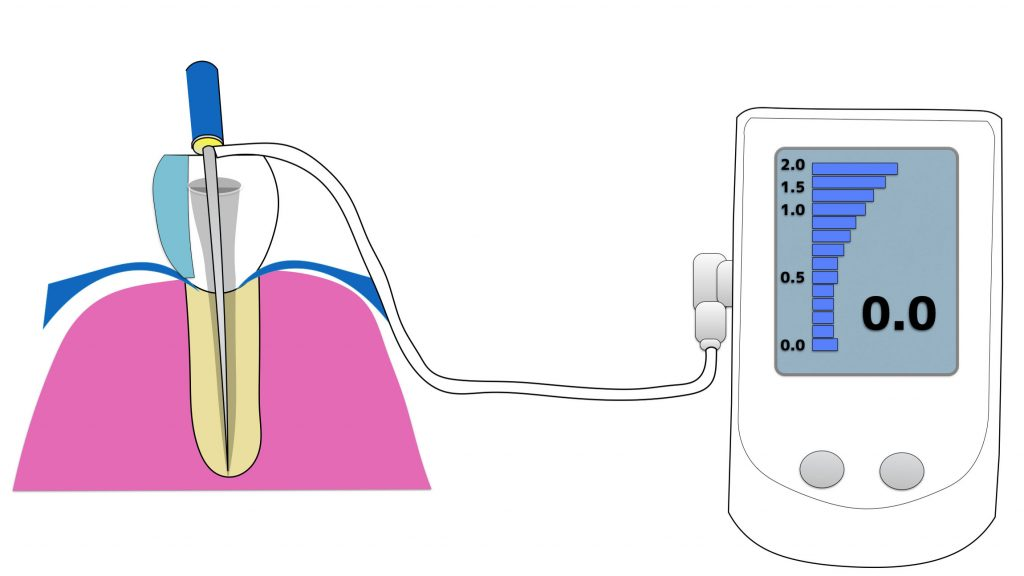

歯の最表層にあるエナメル質は削っても痛みを感じることはありません。象牙質はその内層にあり、また根部ではエナメル質がなく全層が象牙質でできています。象牙質は器具でこすったり、冷たいものや熱いもの等に触れると、その刺激は内部の神経に伝達されて、歯は痛みを感じます。つまり象牙質は痛みを感じる部分です。通常、象牙質はエナメル質に覆われているので、こうした痛みを感じることはありませんが、極端に冷たいものなどではエナメル質の上からでも温度が内部の象牙質に伝わって、歯が痛みを感じることもあります。しかし、様々な理由で象牙質が露出すると、刺激が神経に伝達されやすくなり、知覚過敏が生じるようになります。

象牙質が内部の神経にまで刺激を伝えるのは、象牙質の中にある無数の小さな管状の構造物があることによります。この小さな空隙は加齢などにより、少しずつ塞がってくることもあります。このような場合には知覚過敏は起きません。したがって象牙質が露出している時には必ず知覚過敏が起きるということではありません。

露出した象⽛質の部分に専⽤の薬を塗ったり、専⽤のコーティング剤でカバーしたりすることで、刺激を和らげます。

・象牙質の露出部分を被覆する

知覚過敏のある象牙質表面を被膜で被覆することで知覚過敏をなくすことも可能です。この場合には接着材を用いて樹脂による薄い皮膜を形成するのが通例です。この方法にも即効性があります。象牙質表面がすり減っていたり、酸で溶けていて凹みがある場合には、その凹み部分の形態を回復させるようにして象牙質表面を被覆します。

・神経を取り除く

知覚過敏は一過性の痛みですが、痛みの持続時間が比較的長いような場合や、その痛みが非常に激しい場合には、歯の神経に炎症などの変化が起きていることも疑われます。できれば歯の神経は温存すべきですが、生活に支障が出るようであれば、歯の神経を取り除く治療をすることもあります。